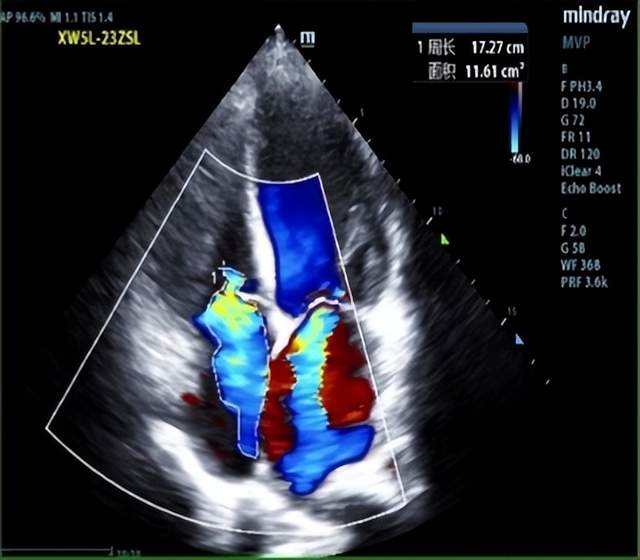

经全面系统检查,张先生被确诊为终末期心力衰竭,同时合并多重严重并发症:难治性心力衰竭D期(心功能IV级,NYHA分级)、冠状动脉粥样硬化性心脏病缺血性心肌病(陈旧性心肌梗死、冠脉支架植入术后)、二尖瓣及三尖瓣重度关闭不全、心房扑动、下肢深静脉栓塞(下腔滤器置入术后),还存在凝血功能异常、肝功能不全、血小板减少等问题,病情复杂危重,传统治疗手段已难以奏效,心脏移植成为唯一救命选择。

术中,患者在全身麻醉下取仰卧位,右侧胸腔垫高30°,手术团队于右侧第三肋间做小切口进胸,借助胸腔镜辅助切开心包并悬吊,清晰暴露手术视野。随后,团队通过左股动脉、右颈内静脉建立体外循环,同步完成肝素化、下腔静脉置管、左心引流等关键操作,为供心植入创造了稳定的生理环境。与此同时,供心获取与修剪工作同步推进,经精准评估,供心发育正常、冠脉走形良好,为移植成功提供了核心保障。

在胸腔镜放大视野下,手术团队严格遵循“由浅到深、由远及近”的操作原则,精准完成左房、主肺动脉、升主动脉等5个关键血管吻合口的双重锁边缝合。这种精细化操作既确保了吻合口的牢固性,有效避免术后出血风险,又杜绝了血管狭窄等并发症,保障了供血通畅。此次手术升主动脉阻断时间仅99分钟,患者全程生命体征平稳。